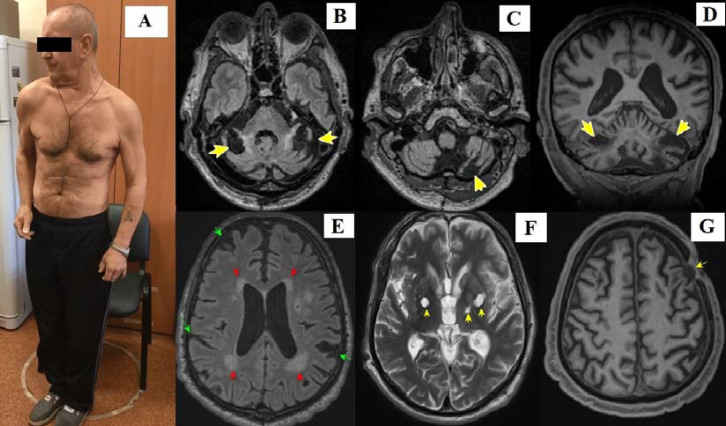

一例罕见的神经梅毒,表现为全身性肌张力障碍伴双侧小脑梗死

A rare case of neurosyphilis presenting as generalized dystonia with bilateral cerebellar infarctions.